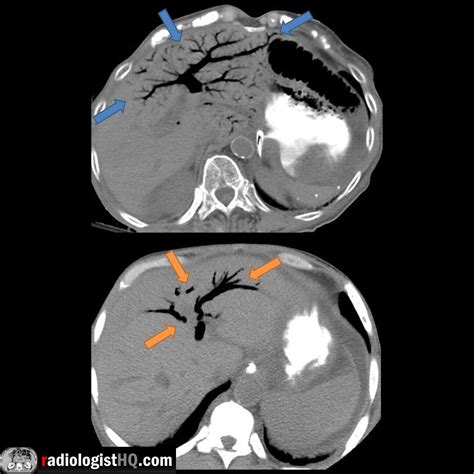

The gold standard for detecting portal venous gas is a CT scan of the abdomen, usually with intravenous contrast. On a scan, gas appears as low-attenuation, branching, linear lucencies that extend into the periphery of the liver. This pattern is distinct from pneumobilia (gas in the bile ducts), which typically resides in the central portion of the liver and follows the path of the biliary tree.

Distribution Extends to the liver periphery Central, follows biliary tree

Clinical Correlation Severe abdominal pathology Common after biliary surgery

Morphology Branching, thin lucencies More rounded, central